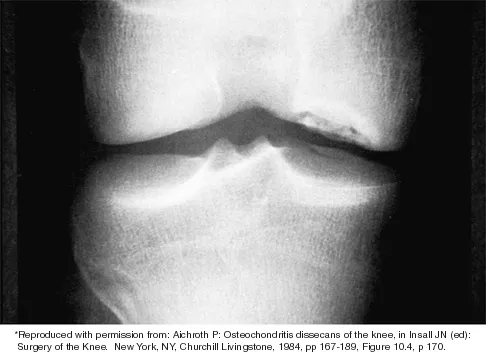

Question 31

Which of the following primary prognostic factors best predicts the outcome of the knee lesion shown in Figure 22?